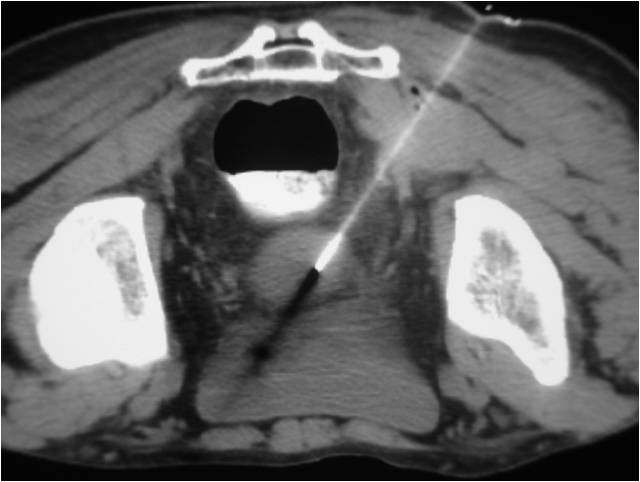

- Placement of a nephrostomy and sump caheter through the greater sciatic foramen into a deep pelvic abscess.

- Paracentisis of a deep pelvic abscess

- Successful catheter placement in a deep pelvic abscess